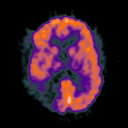

Glioma Overlay -- Slice #12

[Home][Help][Clinical] Slice 12